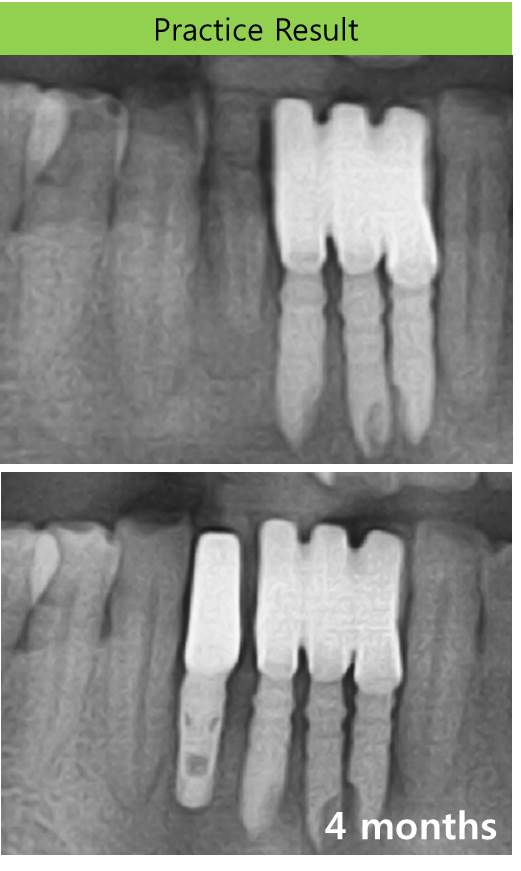

골이식과 임플란트-발치부 골이식과 임플란트-임플란트 식립과 골이식-하악 전치